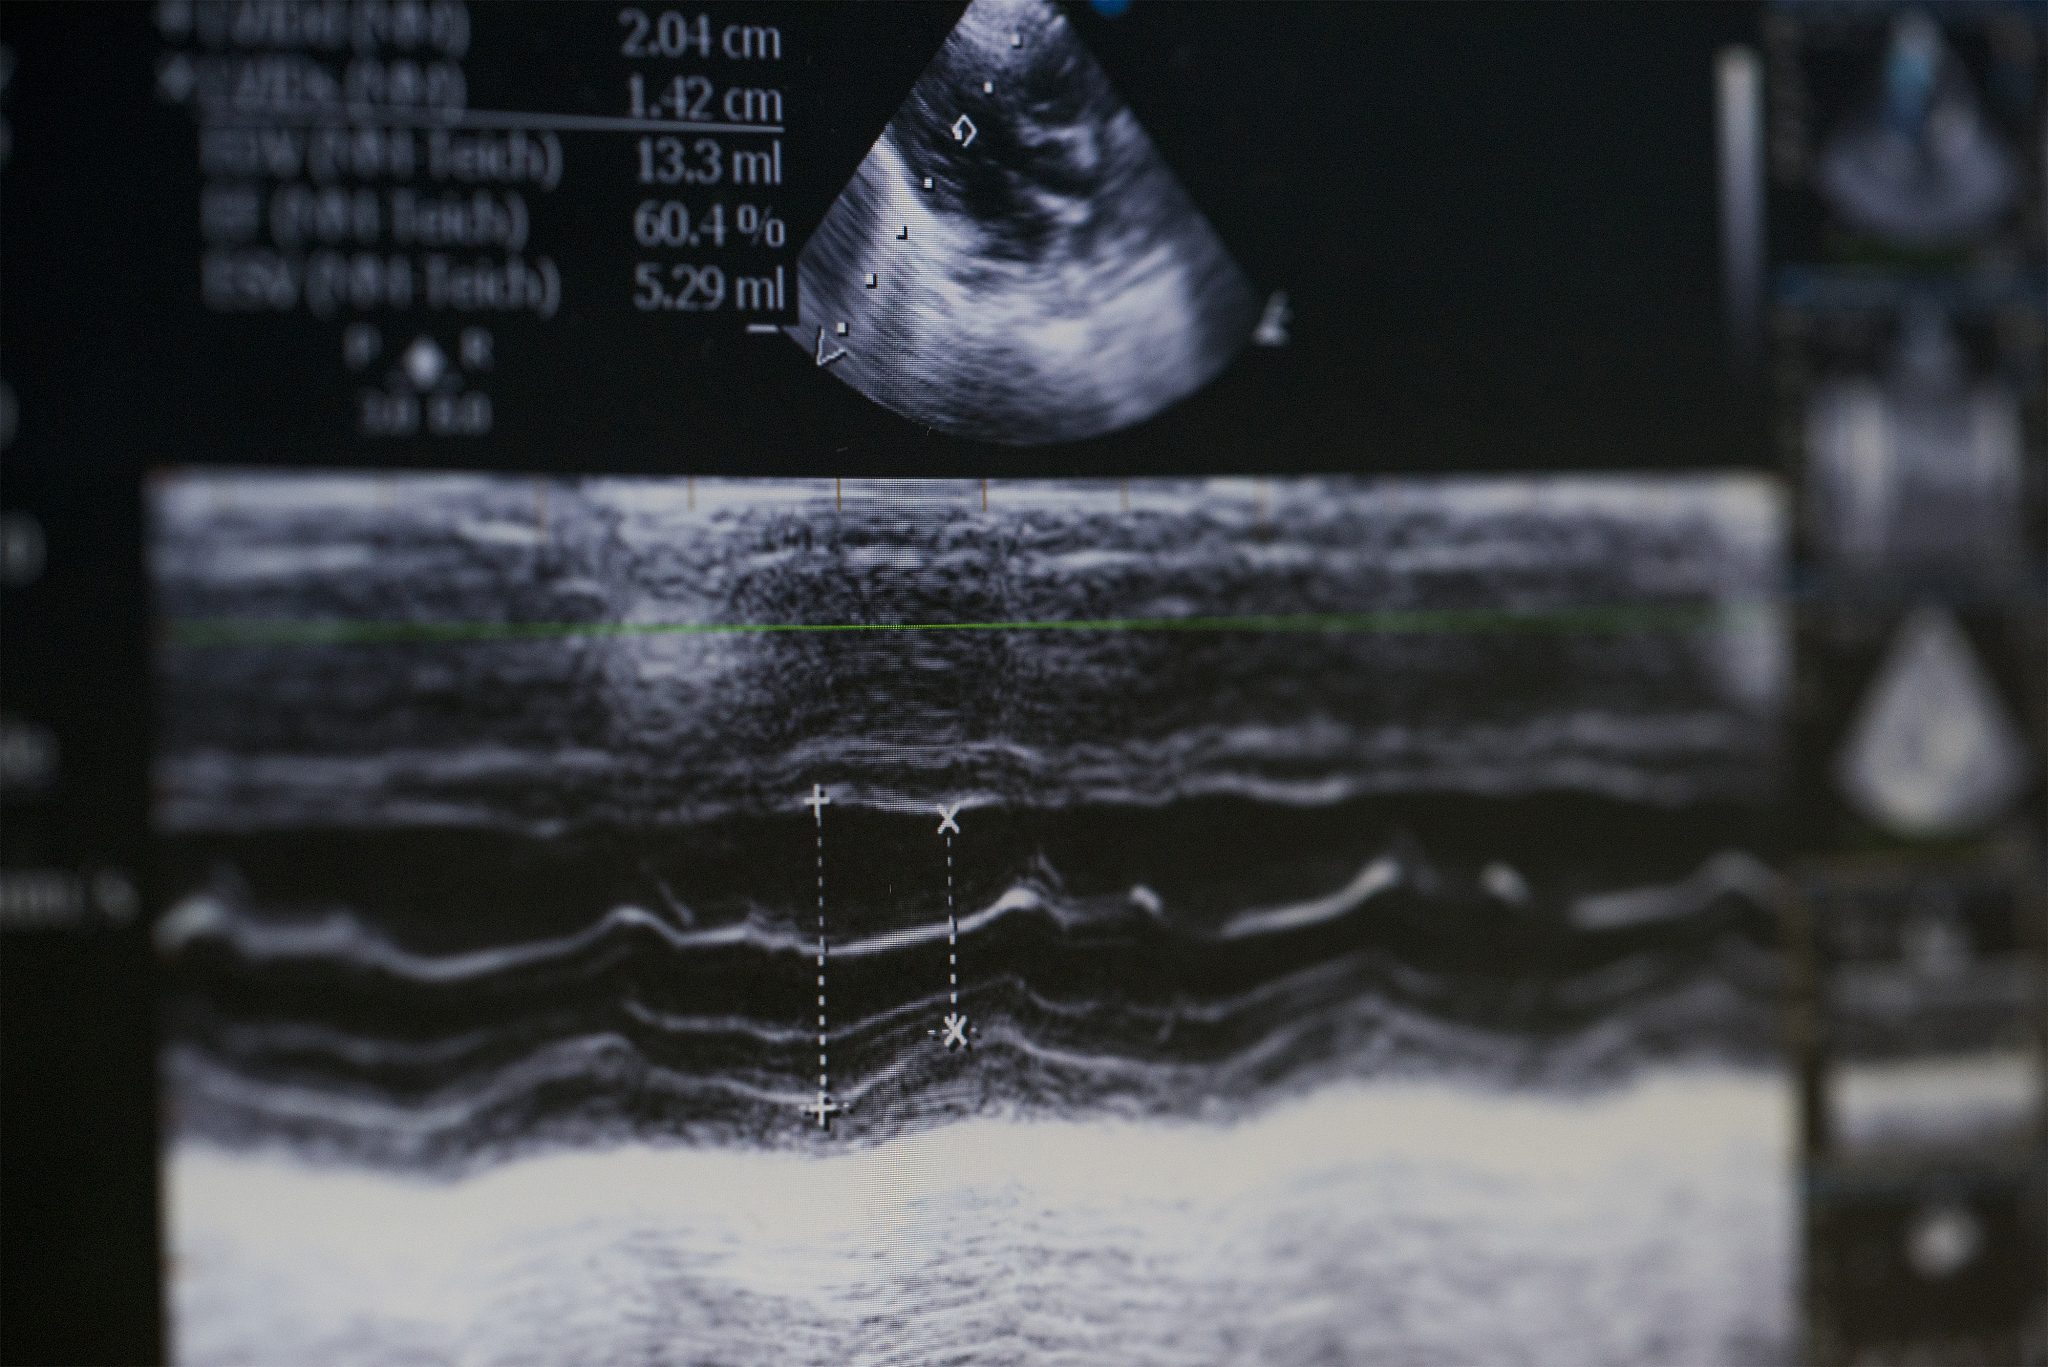

3D超声造影技术可直观显示斑块内溃疡和漂浮血栓

3D超声造影技术可以更加直观地显示斑块内部的'溃疡'和'漂浮血栓'情况。